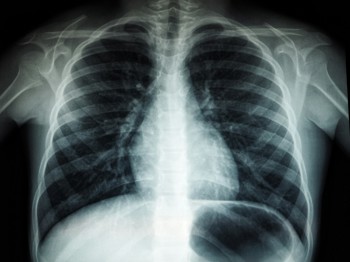

The Community Respiratory Care Team at Wirral University Teaching Hospital identified that people with a history of illicit drug use are at higher risk of respiratory disease than their peers. Their decline into severe disease is more rapid than cigarette smokers and they are more likely to attend hospital. It was also noted that they have poor engagement with traditional models of healthcare.

Drug users were the primary target group because of the lung damage caused by the long-standing habits of smoking heroin (foil smoking) and smoking cannabis – habits that exacerbate the harm arising from smoking tobacco. However, the service also supports alcohol users engaging with Wirral Ways who may have respiratory conditions arising from their smoking.